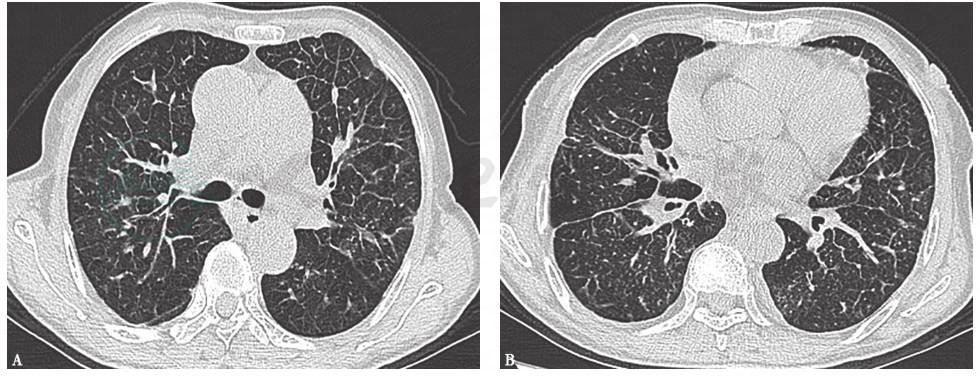

胸部CT示双肺弥漫性间质改变,支气管血管束不均一结节状增粗,从肺门向外周呈放射状,部分分支末梢可到达胸膜,气管前、腔静脉后、隆嵴旁、主动脉旁等纵隔淋巴结肿大,右侧少量胸腔积液(图1)。

图1 胸部CT表现

胸部CT可见双肺弥漫性间质病变,支气管血管束增粗